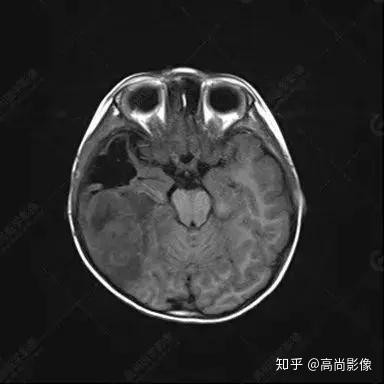

右側(cè)顳葉腫瘤切除術(shù)后(具體不詳):右側(cè)顳部骨質(zhì)不連續(xù)呈術(shù)后改變,右側(cè)顳葉術(shù)區(qū)見片狀長T1長T2信號(hào)影,F(xiàn)LAIR呈低信號(hào);術(shù)區(qū)后方右側(cè)顳枕葉見一巨大占位性病變影,邊界欠清,大小約6.2×5.8×4.3cm(前后×左右×上下),信號(hào)不均勻,T1WI呈等稍低信號(hào)間雜少許高信號(hào),T2WI呈高稍低混雜信號(hào),DWI示部分病灶彌散受限,相應(yīng)ADC圖減低,磁敏感序列見部分呈極低信號(hào),增強(qiáng)掃描可見明顯不均勻強(qiáng)化,鄰近硬腦膜及小腦幕增厚并明顯強(qiáng)化;另延髓右前方及右側(cè)橋小腦角區(qū)見一不規(guī)則形異常信號(hào)影,大小約3.2×1.3×3.7cm(左右×前后×上下),呈長T1稍長T2信號(hào),F(xiàn)LAIR呈等信號(hào),DWI未見受限,增強(qiáng)后明顯均勻強(qiáng)化,鄰近腦膜明顯強(qiáng)化。鄰近腦實(shí)質(zhì)及右側(cè)顳角明顯受壓;左側(cè)大腦半球未見局灶性信號(hào)異常,中線結(jié)構(gòu)稍左移。

右側(cè)顳葉腫瘤切除術(shù)后:現(xiàn)術(shù)區(qū)后方右側(cè)顳枕葉及延髓右前方占位,右側(cè)顳枕部硬腦膜及小腦幕明顯強(qiáng)化,結(jié)合既往影像資料,考慮為胚胎源性惡性腫瘤,如非典型畸胎樣/橫紋肌樣瘤(AT/RT)或原始神經(jīng)外胚層腫瘤(PNET)。